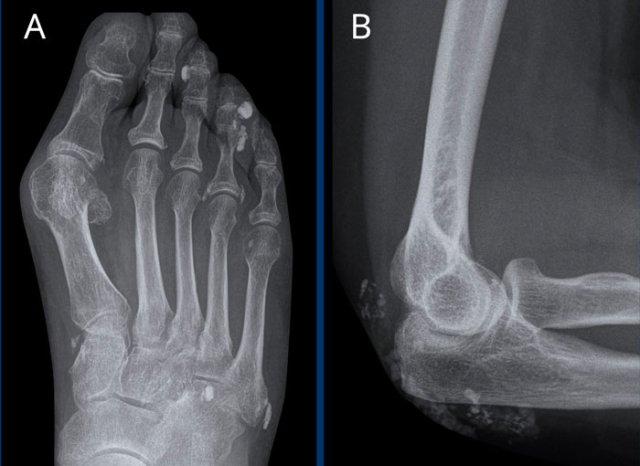

Rheumatoid arthritis in the feet Rheumatoid arthritis in the feet

In this case of rheumatoid arthritis there are marginal erosions adjacent to almost all MTP joints (arrowheads).

The 5th MTP joint is most frequently involved in  rheumatoid arthritis.

When erosions are as severe as in this case, it can look like pencil-in-cup deformity (white arrow) as is frequently seen in psoriatic arthritis.

However, the primarily affected MTP joints distribution and less affected interphalangeal joints is the clue that this is a case of rheumatoid arthritis.

Rheumatic nodule at the elbow Rheumatic nodule at the elbow

Rheumatoid nodules

Rheumatoid nodules are firm lumps that appear subcutaneously in up to 20% of patients with rheumatoid arthritis.

These nodules usually occur adjacent to overexposed joints that are subject to trauma or pressure, such as the fingers joints and elbows.

In this variant of rheumatoid arthritis, there are often no joint abnormalities.

Images

Soft tissue mass (i.e., rheumatoid nodules) in the subcutis at the dorsolateral side of the olecranon.